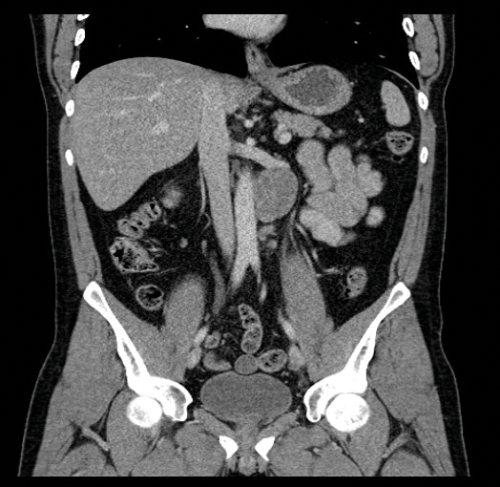

Figure 6. Coronal CT showing left para-aortic lymph node in the same patient as Figure 3.

Nodes may be massive and encase renal vessels, displacing the aorta or inferior vena cava (IVC) and this is important when reporting the staging CT (Figure 5). Coronal views can be very useful to demonstrate the overall length of nodal disease as sometimes, on axial imaging the size of the nodes can be underestimated (Figure 6). Teratoma nodes may contain some areas of calcification or low attenuation areas of necrosis, which are less often seen in seminoma lymph nodes. Retroperitoneal lymph nodes often respond very well to chemotherapy agents, but teratoma nodes may require retroperitoneal lymph node dissection if they do not respond or there remains a sizable node at the end of the treatment.